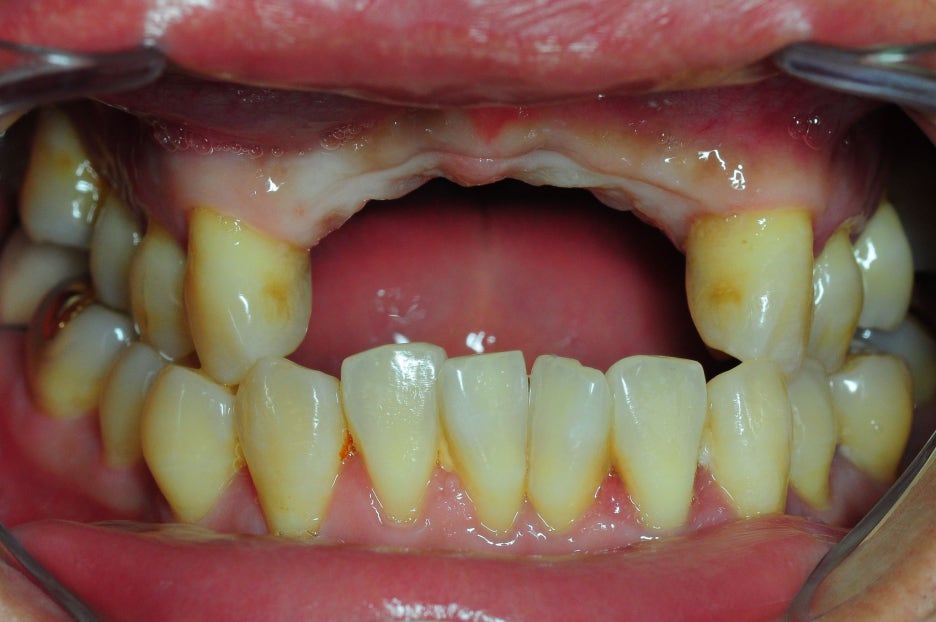

< Some implant surgery cases >

Problem tooth location: mandibular anterior region